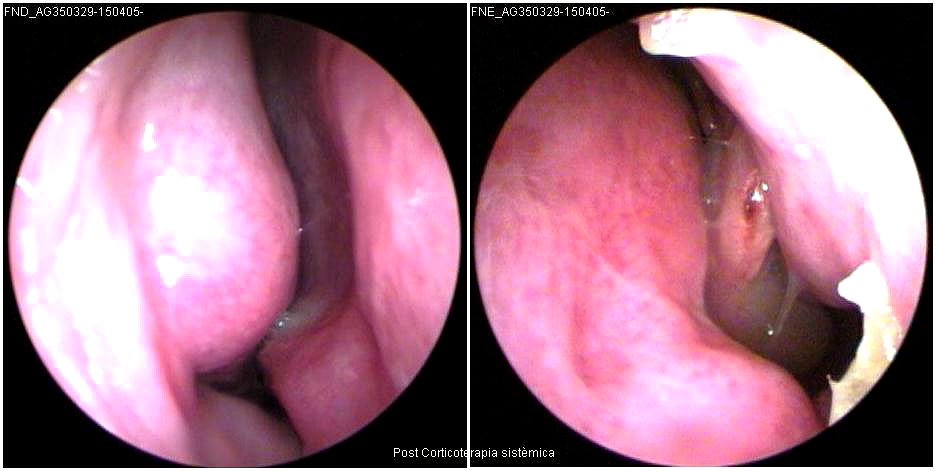

JFC Poliposis nasal bilateral.